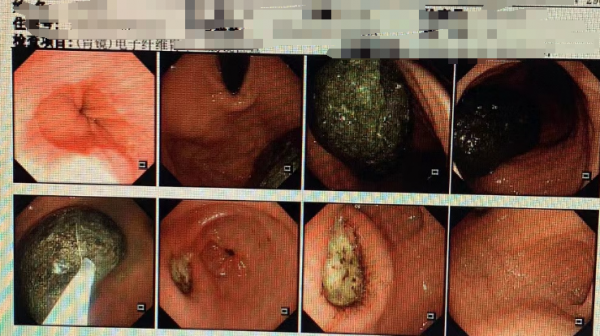

在该院胃肠外科,医生检查发现李女士胃部确实存在一个大胃石。据该院胃肠外科徐晓医生介绍,李女士住院后,医生首选的方案是通过消化内镜,将巨大的胃石破碎成小块分次取出或自然排出。但是李女士的"胃石"非常坚硬,无法通过内镜夹碎。在内镜检查中,医生发现李女士胃部已经被坚硬的"胃石"磨出多处溃疡。为了尽快取出胃石,医生不得不为李女士进行外科手术,取出了这块接近半个手掌大的坚硬"石头"。